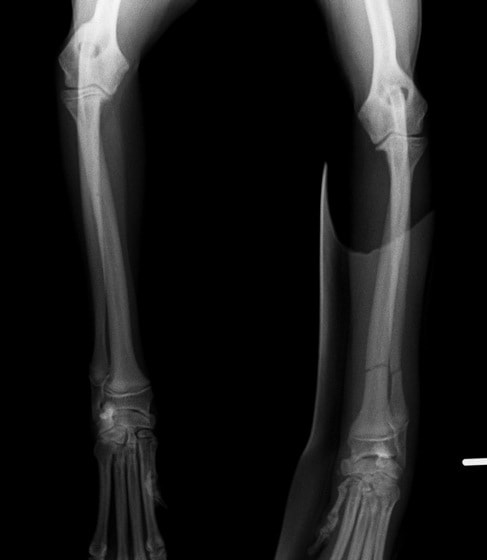

ペルシャ猫 11ヶ月齢 雄

他院にて左大腿骨遠位の成長板骨折(salter-harrisⅠ型)が認められており、治療相談を目的として来院。当院にて、キルシュナーワイヤーを用いたピンニングにより骨折部位の整復を行いました。術後の経過は良好で、現在も経過観察中です。

術前レントゲン